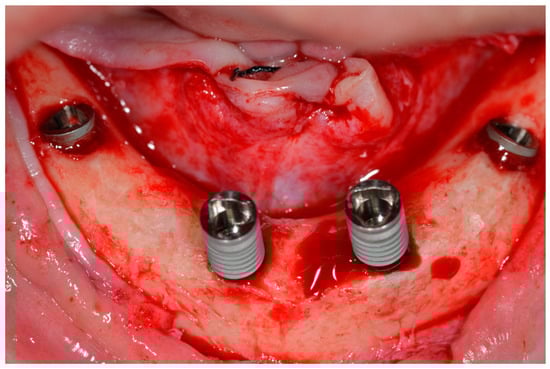

The implants were initially inserted with the handpiece adjusted to an initial IT of 45 Ncm. When the handpiece was stalled, the implant was manually inserted using a custom-made torque wrench [12]. This instrument allowed torques of up to 200 Ncm (Figure 6) to be measured until the implant was completely seated (Figure 7 and Figure 8).

Implants placed according to the All-on-Four concept.

Figure 8.